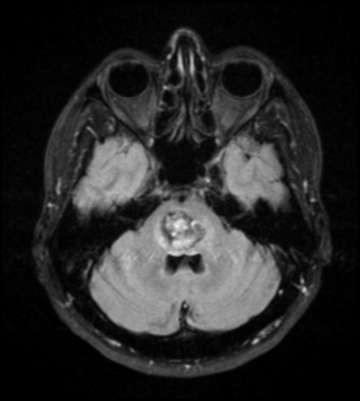

- Magnetic resonance imaging (MRI) is the most sensitive test for identifying cavernous angioma lesions. MRI scans often show small areas of new or old hemorrhages as a rim around the cavernous angioma. These lesions are not visible in cerebral angiography.